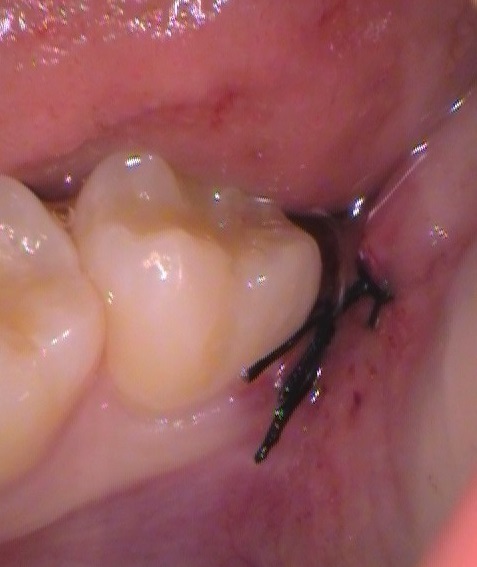

お口の中の写真はこんな感じ。

赤丸の位置に、少しだけ歯の頭が見えます。

上の親知らずはそのまま抜歯を。

下の親知らずは、最小限の歯茎の切開と、歯を分割して取り出してきます。

施術時間:30分以内

抜いた所は、2針縫って傷口を閉じました。1週間後に抜糸をします。